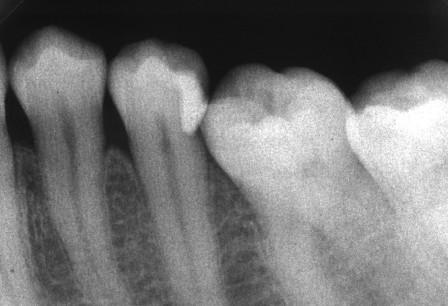

下顎7番の頬側歯茎部カリエスの原因 2025.06.04